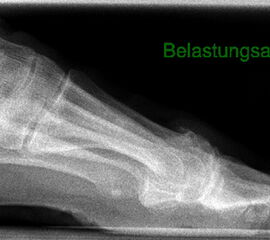

• Röntgenaufnahmen des Vorfußes (unter Belastung) im dorsoplantaren und seitlichen Strahlengang (Abb. 1a+b)

• Beurteilung des Erkankungsstadiums anhand der typischen Arthrosekriterien (Einteilung nach Regnauld). Beurteilung des Intermetatarsal-Winkels (IMA), des Hallux valgus-Winkels (HVA), da nur geringe Korrekturmöglichkeit durch die Osteotomieebene, darüber hinaus evtl. zusätzliche basisnahe MT-I-Korrektur notwendig

• Beurteilung der Grundgliedlänge, insbesondere nach Voroperationen, hinsichtlich möglicher Überlänge des Implantat-Stems.